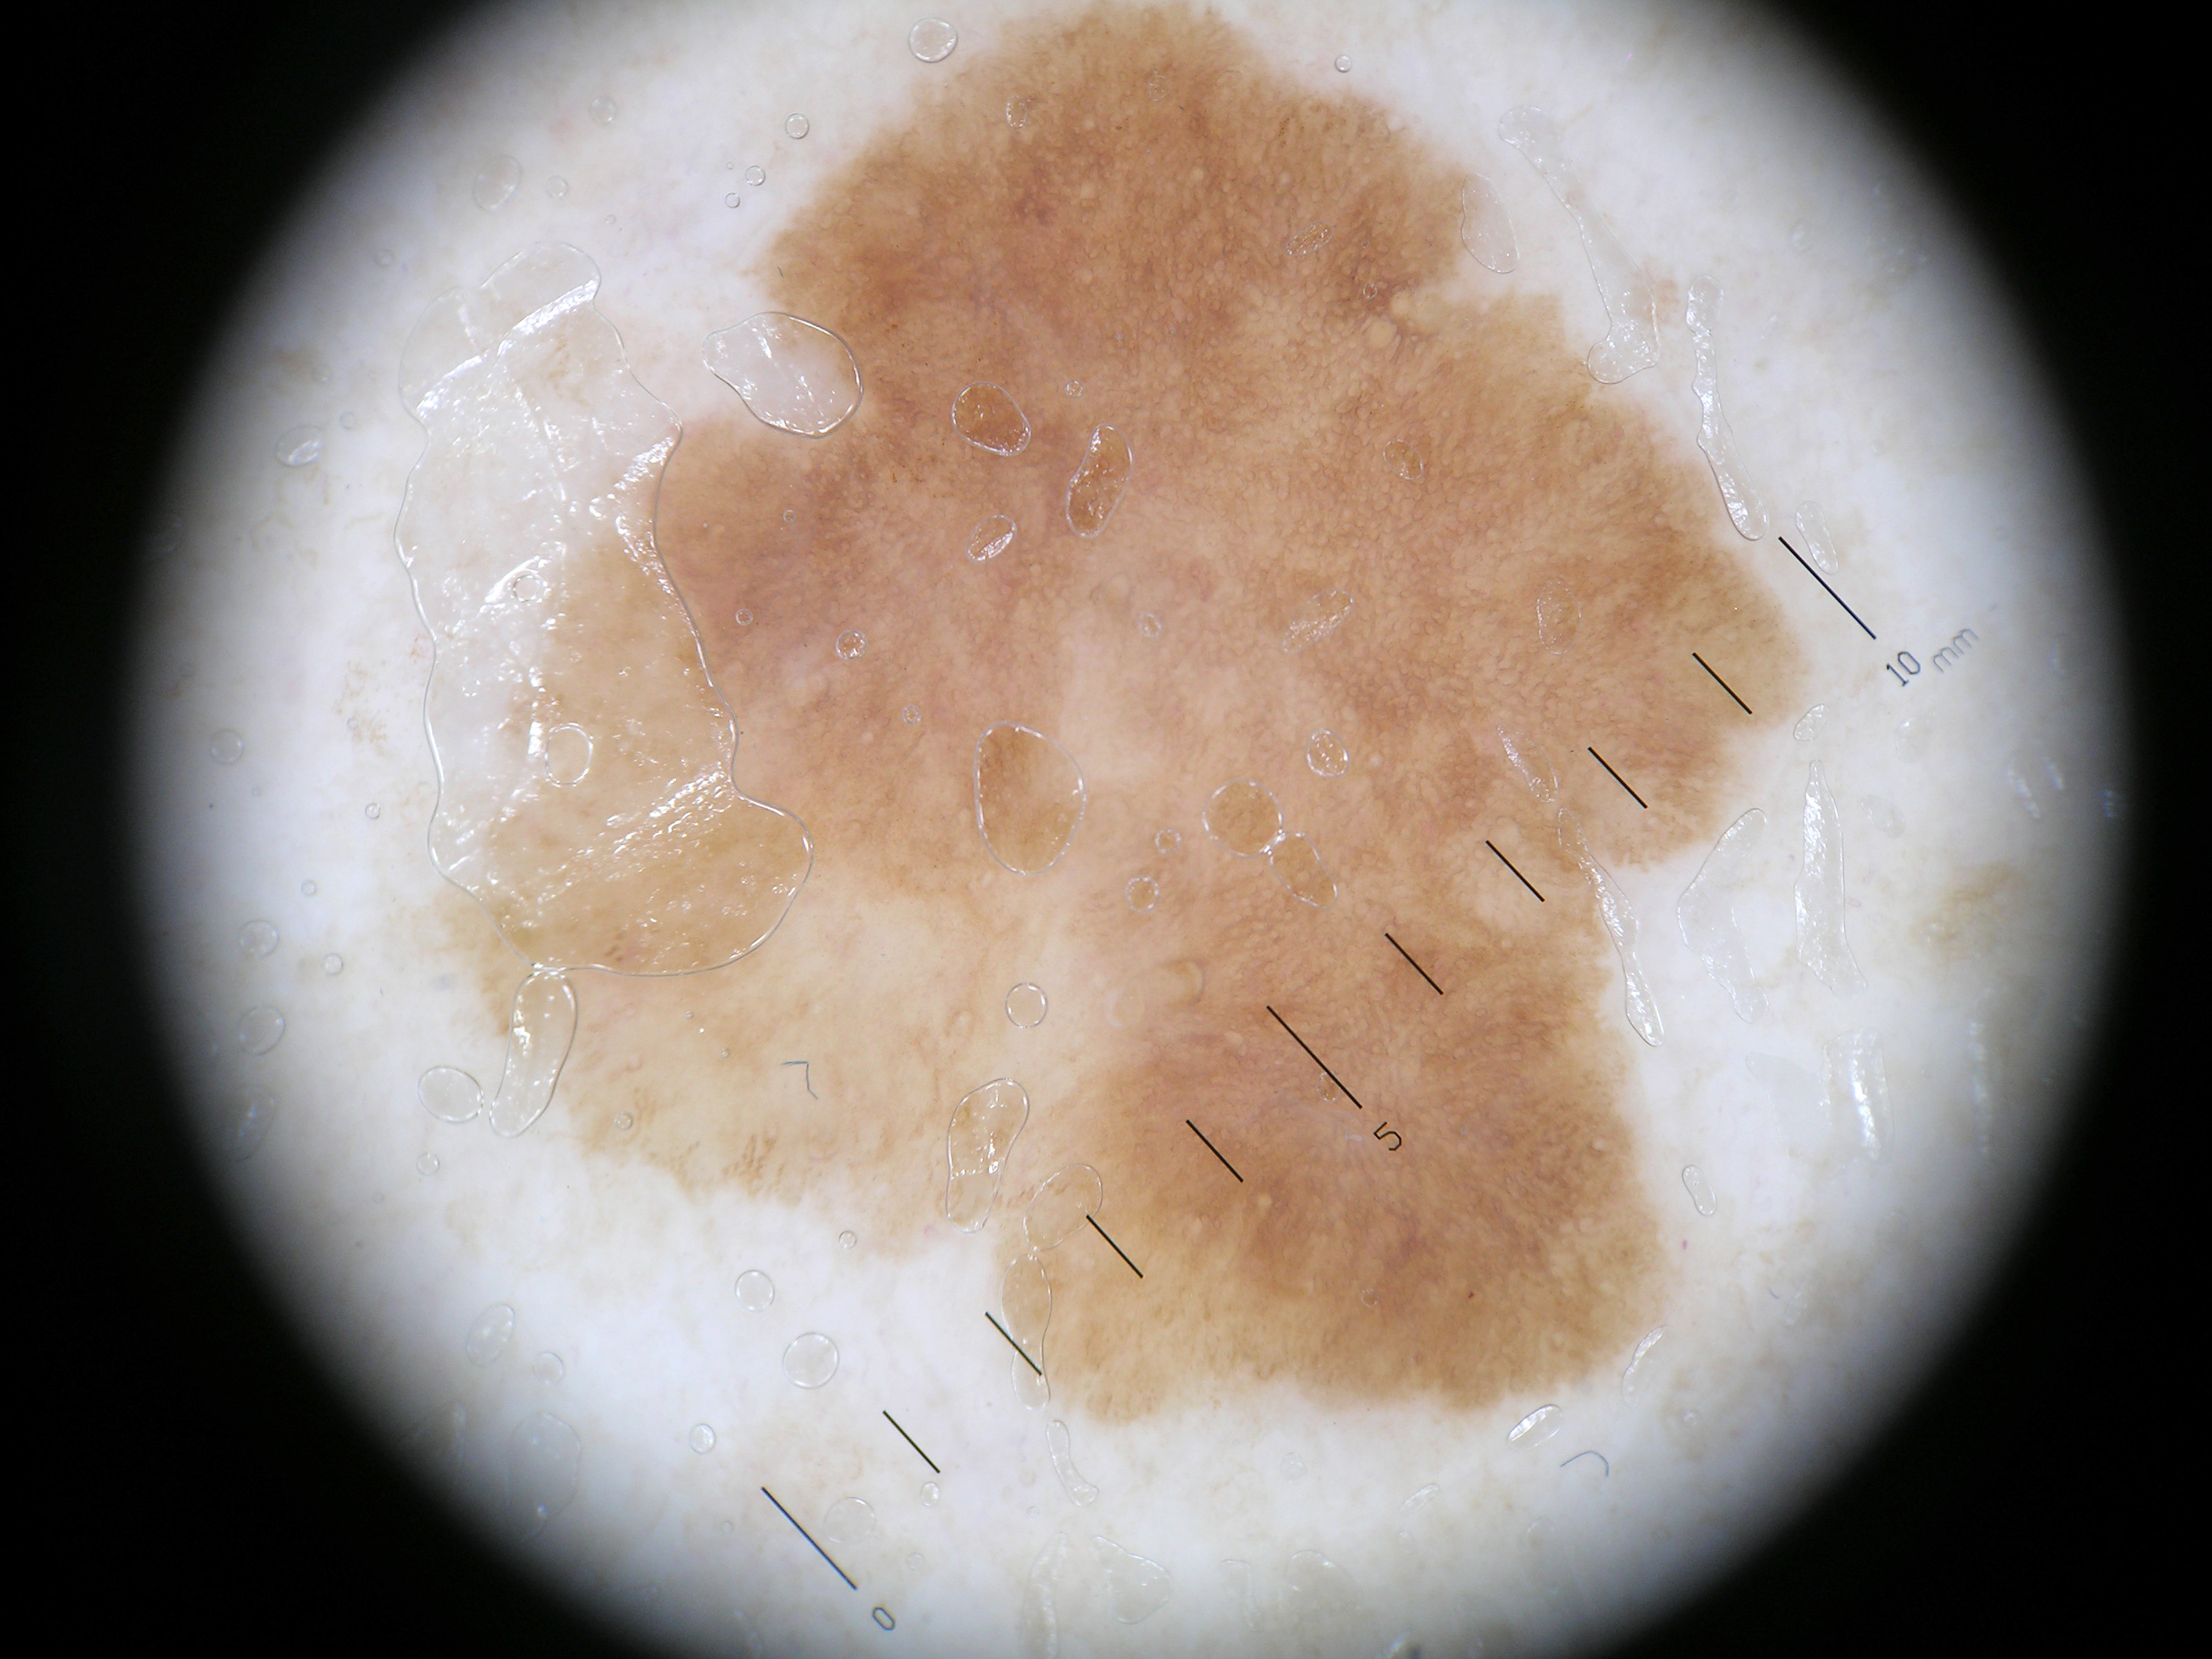

Het

large cell acanthoma is een variant van een

lentigo solaris met als bijzonder histologisch kenmerk dat

de keratinocyten circa 2 keer zo groot zijn als normaal. Klinisch gaat het om

lichtbruine macula of oppervlakkige plaques, enkele mm tot enkele cm groot,

op zonbeschenen gebieden, vooral gelaat en extremiteiten, bij ouderen. Klinisch

lijkt het op een lentigo solaris of op een actinische keratose. Het is een benigne

aandoening. Het gaat wel om een afwijkende celkloon die ontstaan is door sun-induced

DNA schade. Het large cell acanthoma is oorspronkelijk beschreven door

Pinkus als een voorbeeld van 'sunlight-induced clonal growths of abnormal epidermal

cells'. Acanthoma is afgeleid van het Grieks (doorn) en duidt tumoren aan die

uitgaan van het stratum spinosum (stekellaag). In recentere publicaties wordt

large cell acanthoma beschouwd als een lentigo solaris / lentigo senilis met

cellulaire hypertrofie.